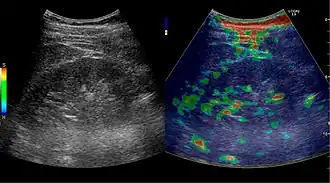

Figure 8. Cortical solid mass, which later was shown to be renal cell carcinoma. Measurement of the solid mass on the US image is illustrated by '+' and a dashed line.[1]

Figure 9. Renal cell carcinoma with both cystic and solid components located in the cortex. Measurement of tumor on the US image is illustrated by '+' and a dashed line.[1]

A solid renal mass appears in the US exam with internal echoes, without the well-defined, smooth walls seen in cysts, often with Doppler signal, and is frequently malignant or has a high malignant potential. The most common malignant renal parenchymal tumor is renal cell carcinoma (RCC), which accounts for 86% of the malignancies in the kidney. RCCs are typically isoechoic and peripherally located in the parenchyma, but can be both hypo- and hyper-echoic and are found centrally in medulla or sinus. The lesions can be multifocal and have cystic elements due to necrosis, calcifications and be multifocal (Figure 8 and Figure 9). RCC is associated with von Hippel–Lindau disease, and with tuberous sclerosis, and US has been recommended as a tool for assessment and follow-up of renal masses in these patients.[1]

However, US is not the primary modality for the evaluation of solid tumors in the kidney, and CT is the first choice modality. Nevertheless, hemorrhagic cysts can resemble RCC on CT, but they are easily distinguished with Doppler ultrasonography. In RCCs, Doppler US often shows vessels with high velocities caused by neovascularization and arteriovenous shunting. Some RCCs are hypovascular and not distinguishable with Doppler US. Therefore, renal tumors without a Doppler signal, which are not obvious simple cysts on US and CT, should be further investigated with CEUS, as CEUS is more sensitive than both Doppler US and CT for the detection of hypovascular tumors.[1]